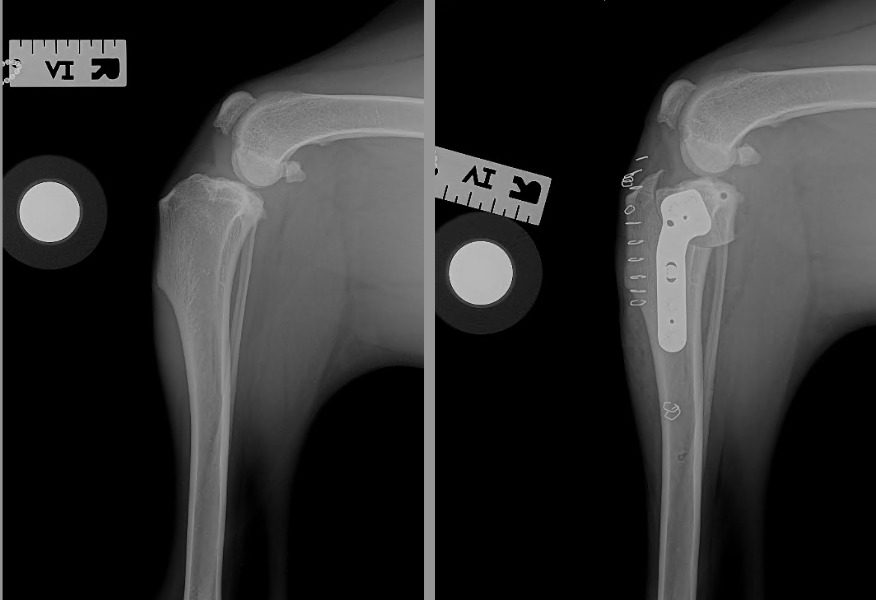

Arthroscopic Surgery before and after